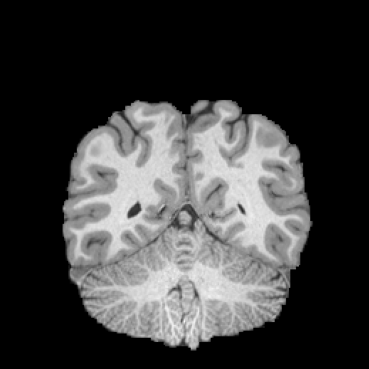

HCP Brain MRI We train on 1076 brain-extracted T1w images from the HCP dataset [24] and test on a sample of 100 pairs between 36 images via mean Dice over 28 midbrain structures [20, 21]. We train and execute the network at [130155130], then compute the Dice score at full resolution.

OASIS Brain MRI We use the OASIS-1 [12] data preprocessed by [9]. This dataset contains images of 414 subjects. Following the data split in [14], we train on 255 images and test on 153 images555Due to changes in the OASIS-1 data, our test set slightly differs from [14]. We evaluate all methods using our testing protocol so that results are consistent.The images in the dataset are of size [160192224], and we crop the center of the image according to the preprocessing in [14], leading to a size of [160144192]. During training, we sample image pairs randomly from the train set. For evaluation, we randomly pick 5 cases as the fixed images and register all the remaining 148 cases to the 5 cases, resulting in 740 image pairs overall.